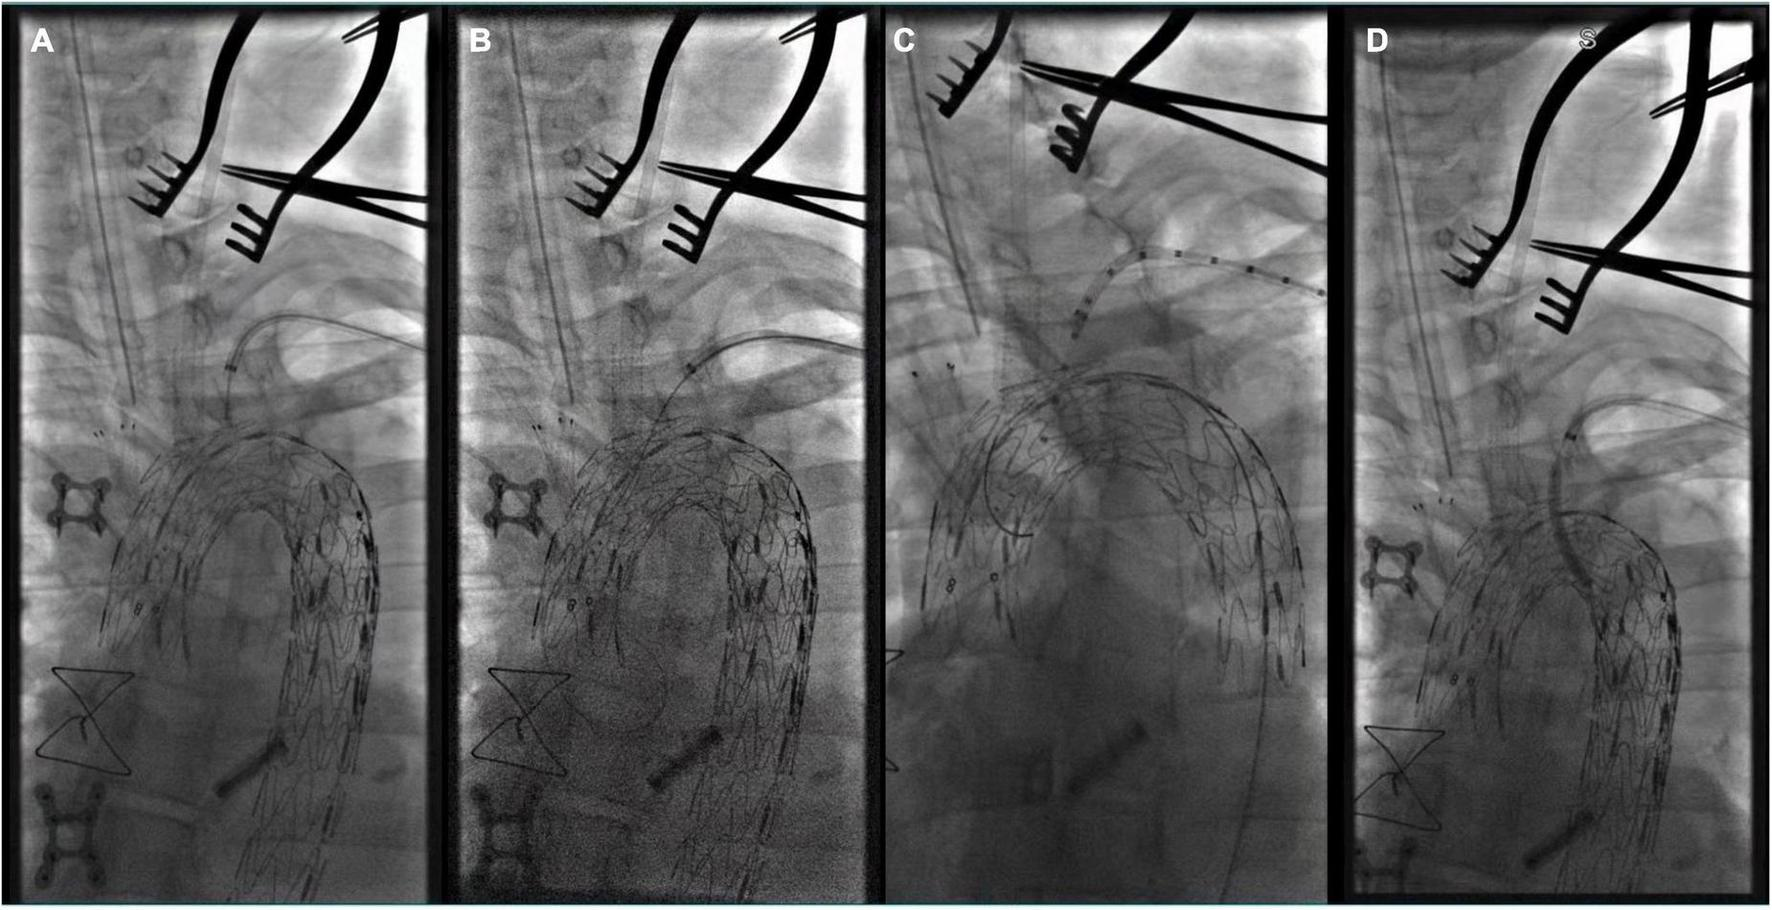

FIGURE 2

Intra-operative angiography after in situ fenestration of the LCA, it was the first branch of the aortic arch to undergo in situ fenestration.